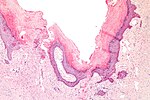

Subdivided into layers:

- Papillary dermis.

- Location: superficial - opposed to the deep aspect of the epidermis.

- Appearance: dense, thick collagen bundles.

- Reticular dermis.

- Location: deep - between papillary dermis and subdermis.

- Appearance: loose connective tissue.